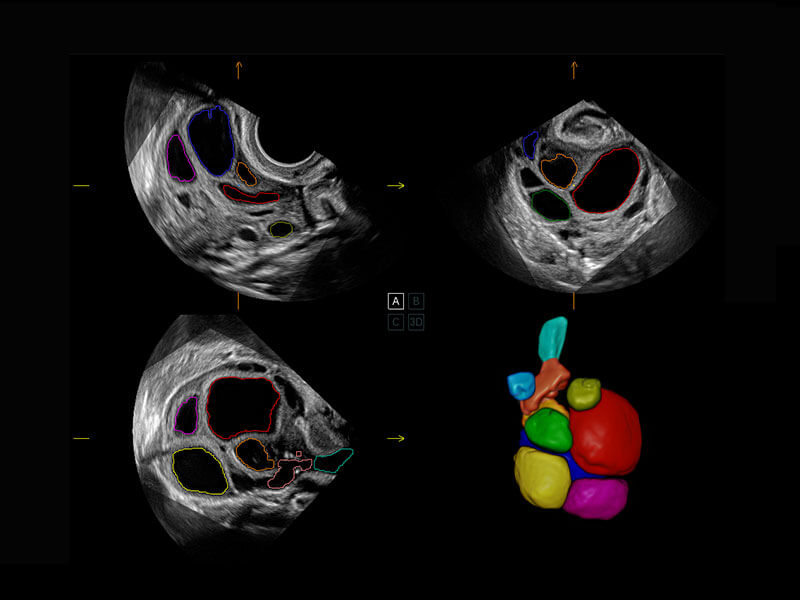

盆底超声

P60为盆底超声检查提供应用方案,多种腔内及腹部容积探头提供从二维、三维到四维的优异图像品质,实时快速三维容积数据获取,专业的测量工具包等人性化设计,为超声医生诊断提供有力保障。

S-Pelvic

能够简化盆底检查的操作流程,可在二维模式及三维成像模式下实现一键自动提取出标准切面、自动识别当前切面、自动测量,提升盆底检查的高效性,同时也能让青年医生快捷的获得准确的检查结果。